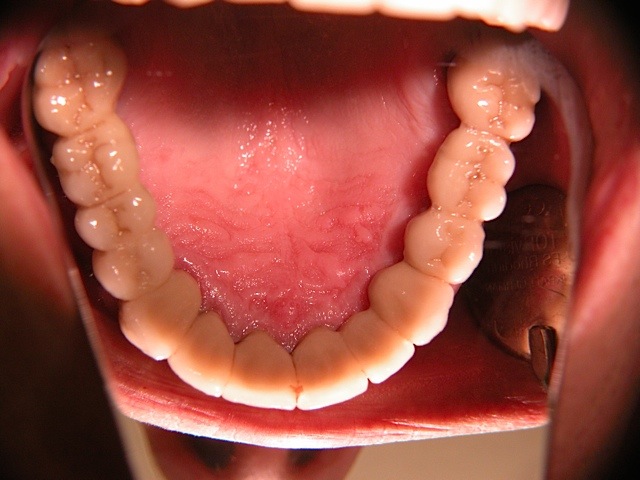

Komplett-Implantation: